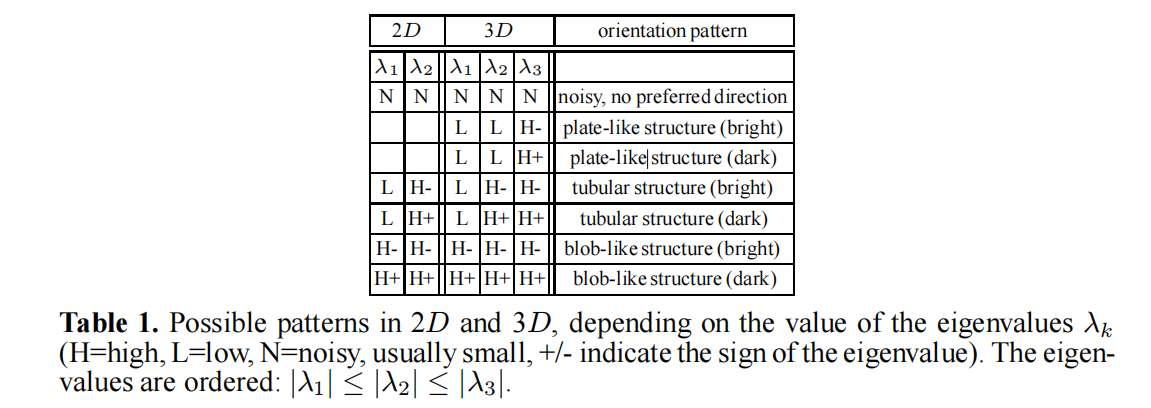

但是説實在的我沒有看明白原理,懵懵懂懂的,反正大概就是知道通過判斷Hessian矩陣的兩個特徵值之間的某些關係可以確定某個位置是否屬於血管或者説管狀結構,我覺得呢大概看懂論文裏這個表可能就比較好了:

我們重點關注2D的情況。

表中Lambda1和Lambda2分別為某個尺度下的Hessian矩陣的特徵值,並且是|Lambda1| < |Lambda2|,對於管狀對象,一般是|Lambda1| << |Lambda2|,其中 <<表示遠遠小於,另外呢,一個先驗就是在血管圖像中背景部分的像素其Hessian矩陣的特徵值一般都比較小,因此,基於這兩個特徵呢,構造了一下兩個中間變量來衡量一個位置的像素是屬於血管還是背景:

對於2D圖像,RB可以簡化為 RB = |Lambda1| / |Lambda2|,而S則即為 S = sqrt(Lambda1^2 + Lambda2^2);